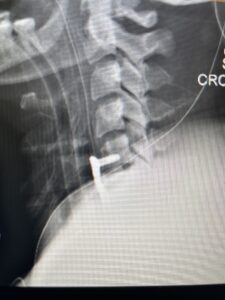

This 47-year-old male who four months prior was lifting weights developed sharp pain in his neck. After that he developed progressive numbness in his arms, neck pain and headache. He said that the right arm was worse than the left. On examination the patient had long tract weakness on the right side which included his triceps, finger extensors, hip flexors, and dorsiflexors. The patient did not have hyperreflexia. MRI (Fig. 2) demonstrated a massive, extruded disc herniation with severe cord compression. The patient because of progressive myelopathy and spinal cord compression was indicated for anterior cervical discectomy and fusion at C4-5 (Fig. 3). Patient had significant improvement of weakness and numbness post operatively.

Fig. 2a Sagittal T2-weighted cervical MRI demonstrating large C4-5 herniated disc with spinal cord compression (red arrow)

Fig: 2b Axial T2-weighted cervical MRI demonstrating spinal cord compression from C4-5 herniated disc (red arrow)